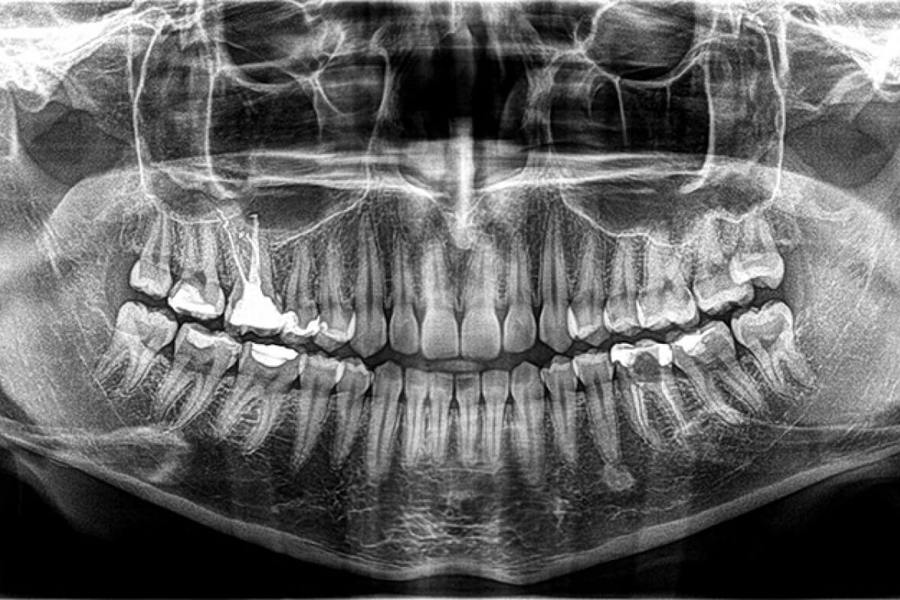

Zahvaljujući naprednoj CBCT (kompjuterska tomografija s konusnim zrakama) tehnologiji u samo 30 sekundi napravit ćemo trodimenzionalni snimak vaših zubnih struktura.

Naš ortopan prikladan je za sve generacije pa tako i za djecu